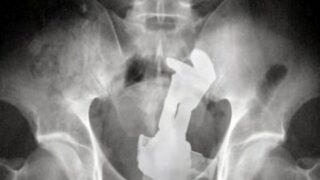

【画像】とんでもないものを挿入れてしまった女の子wwwwwwwwwwwwww Twitter Facebook はてブ LINE コピー 2024.11.25 スポンサーリンク 4:以下、?ちゃんねるからVIPがお送りします:2024/11/24(日) 19:19:21.871 ID:T8oWMks60.net 6:以下、?ちゃんねるからVIPがお送りします:2024/11/24(日) 19:20:29.877 ID:oB+idkf50.net >>4 バズ・ライトイヤーっぽくね 7:以下、?ちゃんねるからVIPがお送りします:2024/11/24(日) 19:21:47.752 ID:k/kIp8pW0.net >>6 マジンガーzかも 続きを読む